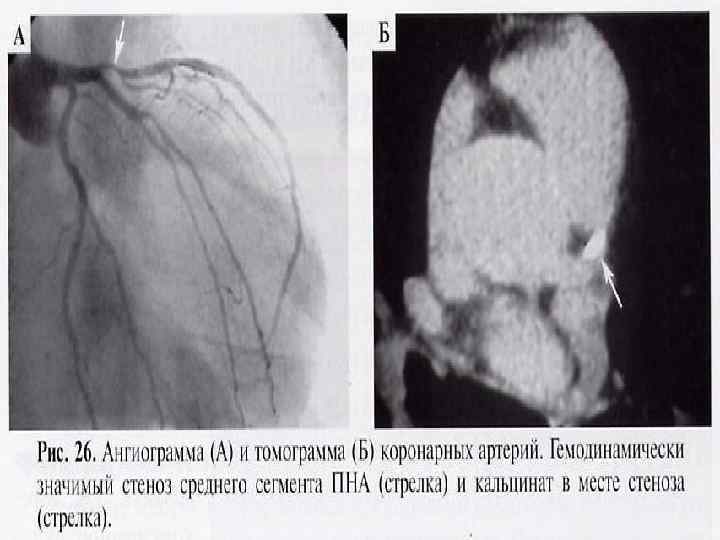

5. УЗИ сосудов 6. Ангиография 7. Компьютерная и магнитнорезонансная томография